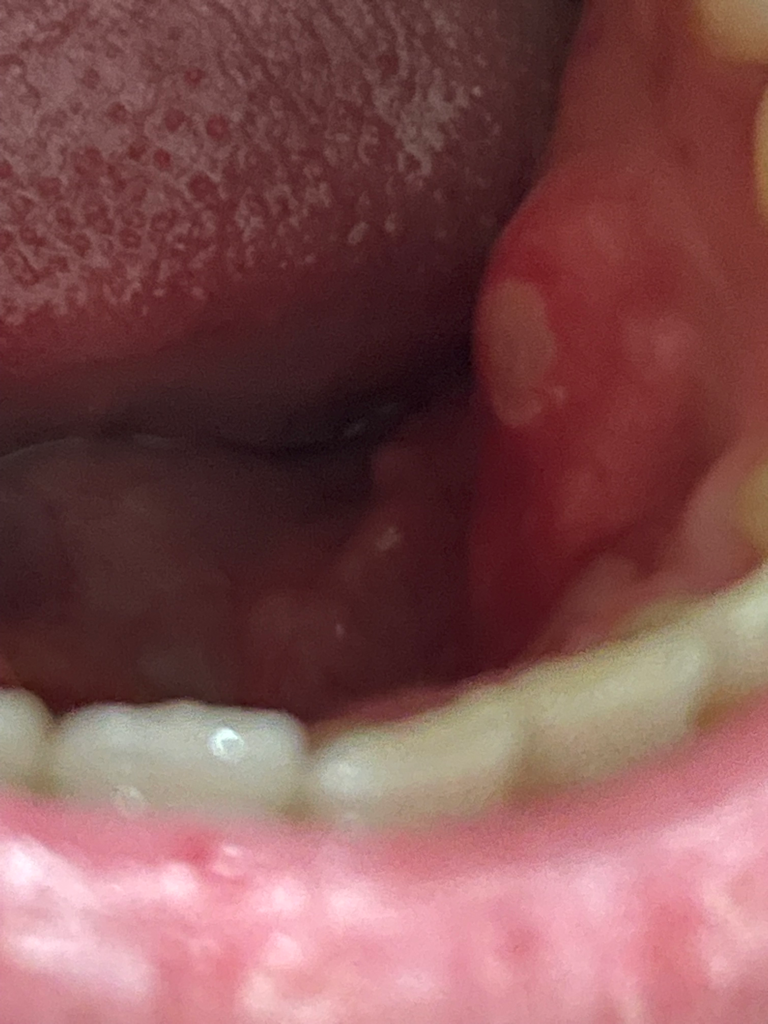

혹시 지금 사진상 이빨 안쪽 잇몸에 구내염이 타원형으로 크게 생겼는데 혹시 매독 가능성이 있을까요?

통증은 안건들고 가만히 있으면 거의 없습니다

매독성 구내염은 매독이 원인인 구내염으로, 입술이나 잇몸에 타원형의 구진이 생기는 것이 특징입니다. 매독성 구내염은 통증이 거의 없고, 2~3주 정도 지나면 자연적으로 치유됩니다. 사진으로만으로는 매독성 구내염인지 여부를 정확히 알 수 없습니다. 만약 매독성 구내염이 의심된다면 병원에서 검사를 받아보는 것이 좋습니다. 매독은 성관계를 통해 전염되는 질환으로, 성관계를 한 적이 있다면 매독 검사를 받아보는 것이 좋습니다. 매독은 초기에 치료하면 완치가 가능하지만, 치료하지 않으면 심각한 합병증을 유발할 수 있습니다.